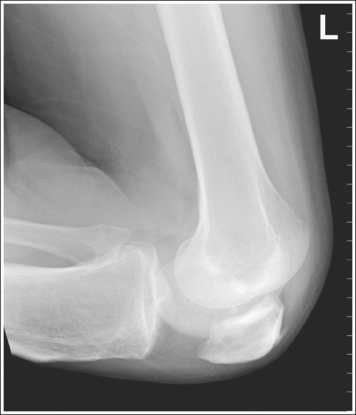

• Distinguishing lateral and medial condyles. The first step you should take when evaluating an image on which the distal condylar surfaces are not aligned is to determine which condyle is the lateral and which is the medial. The most reliable method for identifying the medial condyle is to locate the rounded bony tubercle known as the adductor tubercle. It is located posteriorly on the medial aspect of the femur, just superior to the medial condyle. The size and shape of the tubercle are not identical on every patient, although this surface is considerably different from the same surface on the lateral condyle, which is smooth. Once the adductor tubercle is located, the medial condyle is also identified. Another difference between the medial and lateral condyles is evident on their distal articulating surfaces. The distal surface of the medial condyle is convex, and the distal surface of the lateral condyle is flat.

• Effect of knee rotation on femoral condylar superimposition. When an image is obtained that demonstrates one femoral condyle anterior to the other, the patella must be rolled closer to (leg externally rotated) or farther away from (leg internally rotated) the IR for superimposed condyles to be obtained. The first step in determining which way to roll the knee is to distinguish one condyle from the other. As noted, the most reliable method is to locate the adductor tubercle of the medial condyle. When a lateral knee projection is obtained that demonstrates the adductor tubercle and medial condyle posterior to the lateral condyle, the patella was situated too far from the IR (leg internally rotated) (Figure 6-89; see Image 73). When a lateral knee projection is obtained that demonstrates the medial condyle anterior to the lateral condyle, the patella was situated too close to the IR (leg externally rotated) (Figure 6-90; see Image 74).